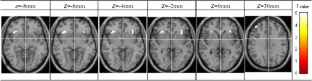

Functional Magnetic Resonance Imaging (fMRI) of inhibitory control has only been investigated in patients with attention deficit hyperactivity disorder (ADHD) and conduct disorder (CD). The objective of this study was to investigate the differences of functional areas associated with inhibitory control between boys with pure oppositional defiant disorder (ODD) and controls during a response inhibition task using functional magnetic resonance imaging (fMRI). Eleven boys with pure ODD and ten control boys, aged 10 to 12, performed a GoStop response inhibition task in this study. The task has a series of “go” trials to establish a pre-potent response tendency and a number of “stop” trials to test subjects’ ability to withhold their responses. During the GoStop task, greater activation in the dorsolateral parts of the bilateral inferior frontal gyrus, left middle frontal gyrus (lMFG) and right superior frontal gyrus (rSFG) activation was seen in the ODD boys. Additionally, reduced activation in regions of the right inferior frontal gyrus (rIFG) was seen in the ODD boys in comparison with the control group. The results may suggest that the higher activation in areas adjacent to the rIFG could be the cause of reduced activation in the rIFG; although this is speculative and requires additional supporting evidence. The findings further suggest that ODD is a less pronounced functional disorder compared to ADHD and CD.

Fig. 2